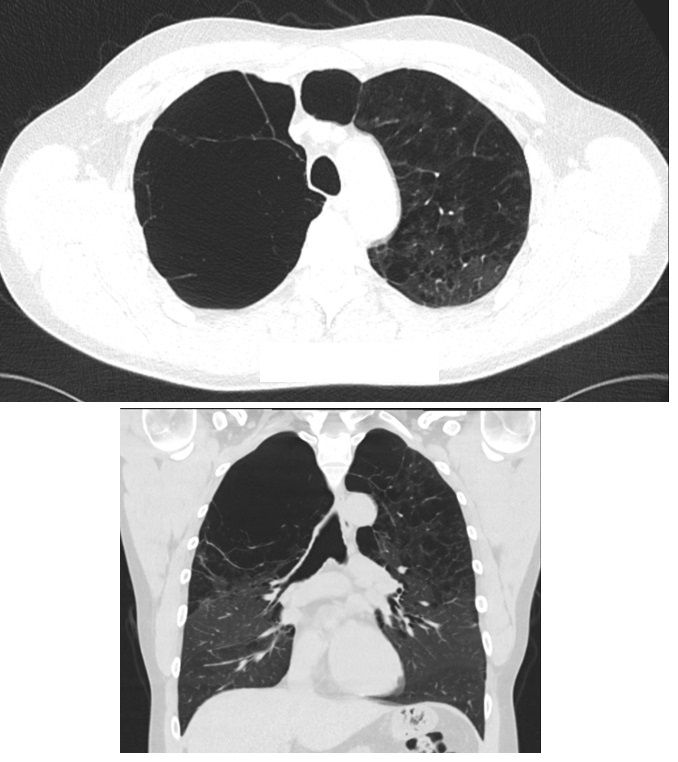

Findings on Chest CT

There are numerous large apical bullae. In addition, there is advanced confluent centrilobular and paraseptal emphysema.